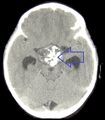

فحوصات التصوير للورم القحفي البلعومي

يمكن للطبيب إجراء بعض الفحوصات والاختبارات لتشخيص الشخص المصاب بالورم القحفي البلعومي.[19] يعد التصوير بالرنين المغناطيسي عالي الدقة (MRI) ذا قيمة لأنه يسمح لأخصائي الأشعة العصبية بمشاهدة الورم من زوايا مختلفة..

في بعض الحالات ، يمكن أن يساعد ماسح التصوير بالرنين المغناطيسي القوي 3T (Tesla) في تحديد موقع هياكل الدماغ الهامة المتأثرة بالورم. يتكون النمط النسيجي من تعشيش ظهارة حرشفية تحدها خلايا مرتبة بشكل اشعاعي. غالبًا ما يكون مصحوبًا بترسب الكالسيوم وقد يكون له بنية حليمية مجهرية. يعد التصوير المقطعي المحوسب (CT) أيضًا أداة تشخيصية جيدة ، حيث يكتشف التكلس في الورم..[20]

في النوع المينائي ، تظهر التكلسات في التصوير العصبي وهي مفيدة في التشخيص.